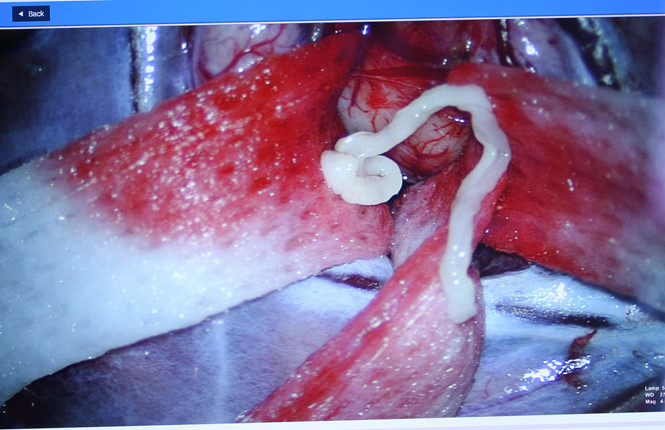

Mới đây các bác sĩ đã cứu 1 nạn nhân thành công sau khi lấy ký sinh trùng dài 7cm ra khỏi não. Được biết trước đó bệnh nhân này bị đau đầu và co giật. Dưới đây là 1 số thông tin đáng chú ý về vụ việc. Bệnh nhân đến bệnh viện khám do đau đầu, yếu nửa người kèm co giật. Các bác sĩ phẫu thuật đã phát hiện và lấy từ trong não bệnh nhân ra kí sinh trùng dài 7 cm.Ngày 20.12, tiến sĩ - bác sĩ Nguyễn Minh Anh, Trưởng khoa Ngoại Thần kinh, Bệnh viện Đại học Y dược TP.HCM (BV ĐHYD), cho biết: anh N.N.A (52 tuổi, ngụ Lâm Đồng) đến khám với những triệu chứng đau đầu, yếu nửa người kèm co giật.

Sau khi người bệnh được thăm khám và thực hiện chụp cộng hưởng từ sọ não, các bác sĩ chẩn đoán anh A. có tổn thương choán chỗ vùng vỏ não vận động có thể do u hoặc nang kí sinh trùng trong não.Khi ca phẫu thuật được thực hiện, các bác sĩ đã xác định chính xác bệnh lý của anh A. là u nang kí sinh trùng trong não.

Các bác sĩ đã lấy được kí sinh trùng dài khoảng 7 cm trong não người bệnh.

Kết quả giải phẫu bệnh cho thấy đây là loại kí sinh trùng có tên khoa học là Spirometra erinaceieuropaei hay còn gọi là sán nhái.